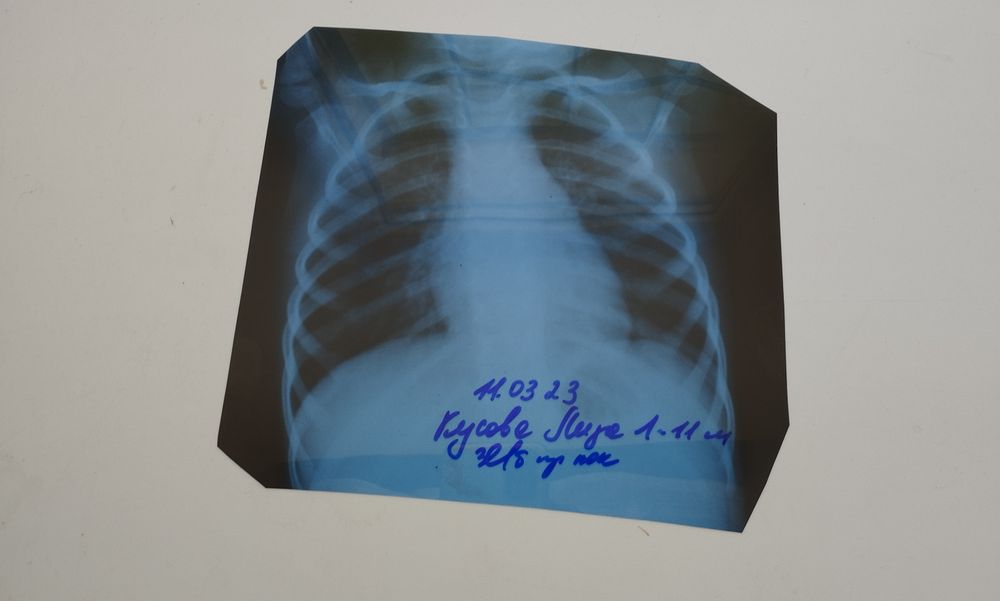

Заболели! Все об ОРВИ :(Здравствуйте. Приходила у нас дежурная врач. Услышала хрипы слевой стороны внизу... Отправила в инфекционное отделение. Нам там дали направление на рентген, и сказали, сделаете рентген и в понедельник к своему врачу на приём в поликлинику.... Ни о какой госпитализации нет речи. Сделали мы рентген, дали нам снимок и отправили домой... Не знаю понятно ли будет по фото что то. Но может все таки кто то разбирается. Есть ли тут пневмония ?! Я до понедельника с ума сойду.

Очагов пневмонии нет, но увеличены грудные лимфоузлы. Возможно бронхит или трахеобронхит.

Я не врач, но мой ребенок переболел пневмонией только что. На снимке она выглядит совершенно по-другому, там легкое не видно, а у вас легкие четкие на снимке, на мой дилетантский взгляд, нет никакой пневмонии